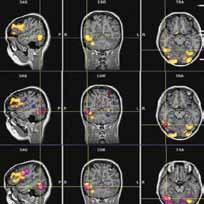

as an affiliate faculty member at the Center for advanced study of language (Casl), bolger’s current research project explores the phenomenon of brain training. with this study, he and a cohort of university of maryland faculty are looking at the effects of cognitive training on the brain specifically when participants are asked to engage daily in 15 to 30 minutes of working memory exercises over a course of five weeks. he’s been responsible for the brain imaging portion of the project using the fmRi scanner in the university’s new maryland neuroimaging Center. bolger’s

team takes a brain image before and after the five weeks of training. “we’re looking for changes in the activation of the brain areas. what areas change? we’re also looking at not just kind of the patterns of activation, but if these regions change structurally. are these areas growing? we measure the white matter (fatty tissue that forms the insulation on the neurons allowing them to transmit faster) to see if these fiber pathways are better insulated because of this workout.”